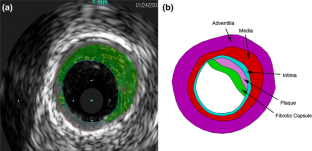

Wall injury is observed during stent expansion within atherosclerotic arteries, related in part to stimulation of the inflammatory process. Wall stress and strain induced by stent expansion can be closely examined by finite element analysis (FEA), thus shedding light on procedure-induced sources of inflammation. The purpose of this work was to use FEA to examine the interaction of a coiled polymer stent with a plaque-containing arterial wall during stent expansion. An asymmetric fibrotic plaque-containing arterial wall model was created from intravascular ultrasound (IVUS) images of a diseased artery. A 3D model for a coil stent at unexpanded state was generated in SolidWorks. They were imported into ANSYS for FEA of combined stent expansion and fibrotic plaque-distortion. We simulated the stent expansion in the plaqued lumen by increasing balloon pressure from 0 to 12 atm in 1 atm step. At increasing pressure, we examined how the expanding stent exerts forces on the fibrotic plaque and vascular wall components, and how the latter collectively resist and balance the expansive forces from the stent. Results show the expanding coiled stent creates high stresses within the plaque and the surrounding fibrotic capsule. Lower stresses were observed in adjacent medial and adventitial layers. High principal strains were observed in plaque and fibrotic capsule. The results suggest fibrotic capsule rupture might occur at localized regions. The FEA/IVUS method can be adapted for routine examination of the effects of the expansion of selected furled stents against IVUS-reconstructed diseased vessels, to improve stent deployment practices.

Figure 1